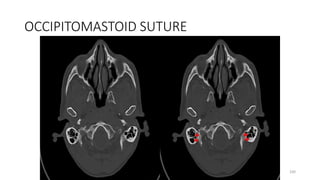

OCCIPITOMASTOID SUTURE

OCCIPITO MASTOID SUTURE